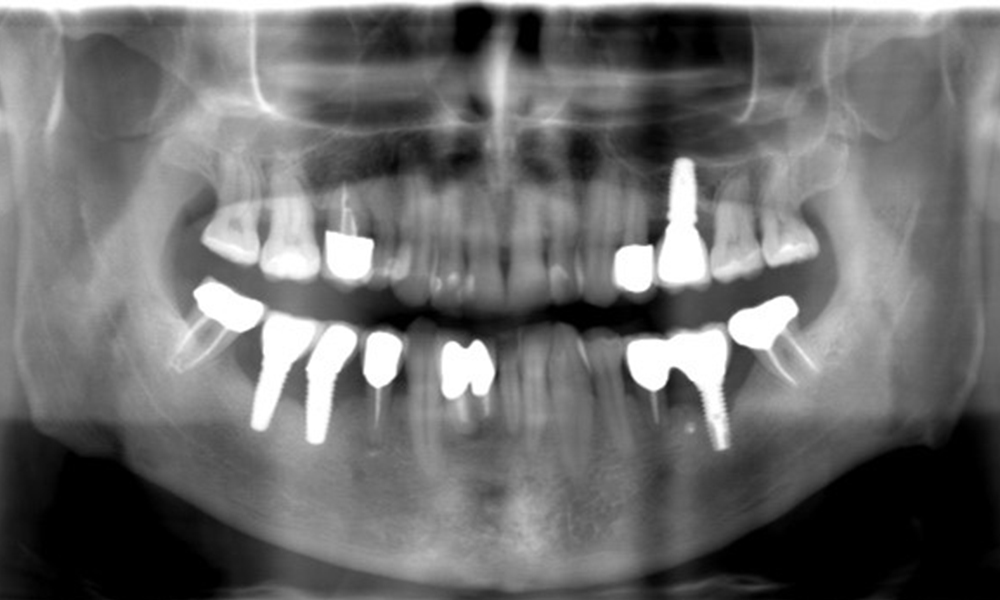

Ein 52-jähriger Patient stellt sich zur Präventionssitzung vor. Der Patient hat keine Allgemeinerkrankungen und nimmt keine Medikamente ein. Er hat verschiedene zahnärztliche Versorgungen und zudem zwei aktive kariöse Läsionen. Außerdem verfügt der Patient über vier Implantate (2., 3. und 4. Quadrant). Es zeigt sich eine parodontale Vorerkrankung (Stadium IV, Grad B). Derzeit herrschen stabile parodontale Verhältnisse, lediglich am Implantat regio 36 zeigen sich Sondierungstiefen (ST) von 5 mm. Zudem lässt sich eine Gingivitis feststellen.

Der Patient zeigt keine besonderen anamnestischen Risikofaktoren mit spezifischen zahnmedizinischen Auswirkungen. Daher ist der aus der Mundgesundheit ermittelte Bedarf maßgebend. Hierbei zeigt sich am Implantat im 3. Quadranten ST von 5 mm und im Röntgenbild eine Zunahme des Knochenverlustes. Der Patient hat zudem eine aktuell stabile parodontale Vorerkrankung und zwei aktive initialkariöse Läsionen.